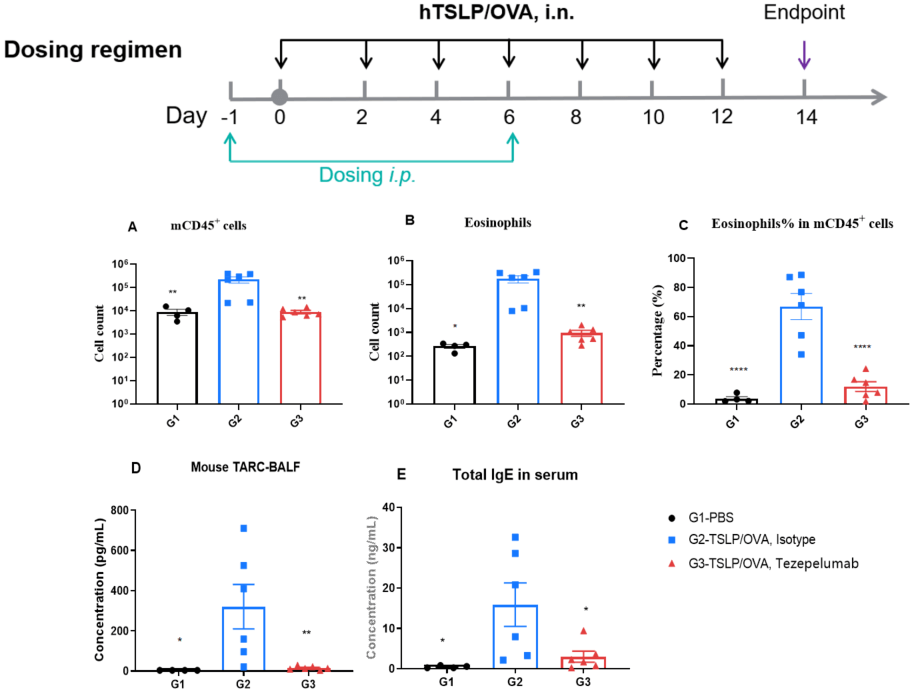

H&E staining and histopathological scoring of lung tissue in TSLP/OVA-induced asthma model of TSLP and TSLP receptor humanized (B-TSLP/TSLPR) mice. Compared to G1 (PBS-treated controls), G2 (TSLP/OVA + isotype) mice exhibited hallmark asthma pathology, including vascular and peribronchial mixed inflammatory cell infiltration (b) and mucus accumulation (a) in bronchi. Tezepelumab treatment in G3 (low dose) and G4 (high dose) reduced airway inflammation and mucus secretion in a dose-dependent manner. Increased inflammatory cell infiltration, mucus production, and eosinophil presence were observed in G2, all of which were attenuated by anti-TSLP therapy, supporting the efficacy of tezepelumab in this allergic asthma model.